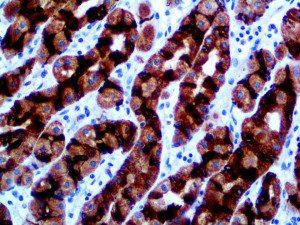

The first cytokines released are interleukin 1β (IL-1β) and tumor necrosis factor-α (TNF-α), which attract a variety of circulating white blood cells (WBCs) to the infection site, including neutrophils, monocytes, macrophages, and natural killer (NK) cells. This response, along with the antipathogenic chemicals released by these cells (i.e., complement), comprise the innate immune response. These cells directly attack the invading pathogen and also release additional cytokines, chief among them interleukin-1 and 6 (IL-6). IL-6 is essential for invoking the adaptive immune response, which calls T-cells, B-cells, and T helper (Th) cells to the infection site. IL-6 also stimulates further recruitment, proliferation and activation of macrophages.

It is the ICU physician who is most likely to witness one of the deadliest manifestations of the abnormal immunological response, the cytokine storm syndrome (CSS). This response is also referred to by some as the cytokine release syndrome (CRS). CSS is characterized by continuous activation and expansion of macrophage and lymphocyte populations, which secrete large amounts of cytokines, causing the cytokine storm. This massive cytokine release is akin to hemophagocytic lymphohistiocytosis (HLH) disease, a syndrome characterized by initial unchecked and persistent activation of cytotoxic T lymphocytes and NK cells.

This activation induces inflammatory monocytes to highly express IL-6, starting a localized and then systemic cascade effect that results in hyperproduction of IL-6, which accelerates the inflammatory process. Because IL-6 also increases vascular permeability, excessive levels cause blood vessels to become very leaky. This, along with clotting factors released from vascular endothelial cells, stimulates the coagulation cascade, resulting in microthrombosis (tiny clots), which leads to ischemia and tissue death of the kidney, intestines, heart, liver, brain and extremities.